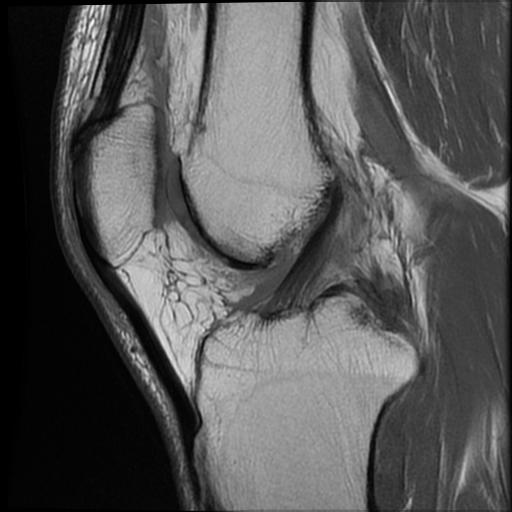

Normal ACL on MRI

Characteristics

- straight structure

- able to see continuity of fibres from tibial to femur

- parallel to intercondylar notch

- no anterior subluxation of the tibia

- normal to have some increased signal due to adipose and synovial tissue

Sagittal TI MRI with no femoral attachment